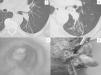

Clinical CaseThe patient was a 63-year-old man, ex-smoker for 36 years (40 pack-years), with a history of bronchial asthma. He had symptoms of a dry cough and intermittent dyspnoea, and was being monitored in the Respiratory Medicine department for bronchiectasis. A routine computed tomography (CT) scan for his respiratory disease highlighted the presence of an endobronchial lesion in the left lower lobe (Fig. 1A). Fibrobronchoscopy was subsequently performed, showing an endoluminal lesion in the lower bronchus. No malignant neoplastic signs were detected in either the biopsy or cytology, despite repeating these studies on a further two occasions. In view of these findings and the absence of symptoms, it was decided to maintain clinical and radiological follow-up. In the last few months, he had episodes of haemoptysis and persistent respiratory infections that improved with antibiotic treatment. New imaging tests (Fig. 1B) and an endoscopic examination (Fig. 1C) revealed an increase in the size of the polypoid lesion extending towards the left main bronchus, more than 2cm from the main carina. Acute inflammatory changes were also observed on this occasion, both in the bronchial aspirate and in the bronchial biopsy, with no neoplastic cells detected.

(A) An endobronchial lesion can be observed in the left lower lobe at the level of the interlobar carina on the chest CT scan. (B) Chest CT scan one year later: growth of the endobronchial lesion towards the lumen of the main bronchus can be seen. (C) Fibrobronchoscopy: endobronchial lesion protruding towards and partially occluding the lumen of the main bronchus. (D) Surgical specimen: polypoid lesion originating from the lower lobe bronchus.

Due to the suspicion of a malignant lesion and the difficulty in obtaining a diagnosis, it was decided to operate on the patient. A video thorascopic examination was performed, observing the presence of signs of hepatisation and fibrosis in the lower lobe, as well as the presence of multiple firm adhesions mainly in the costodiaphragmatic recess, which prevented the examination from being completed. A left lower lobectomy was eventually performed by lateral thoracotomy. When the lower bronchus was sectioned, a 2cm yellow pediculated tumour with smooth borders was identified, originating from the walls of the lower lobe bronchus and protruding towards the lumen of the main bronchus (Fig. 1D). The patient did not present any complications during the post-operative period and was discharged on the fifth day.